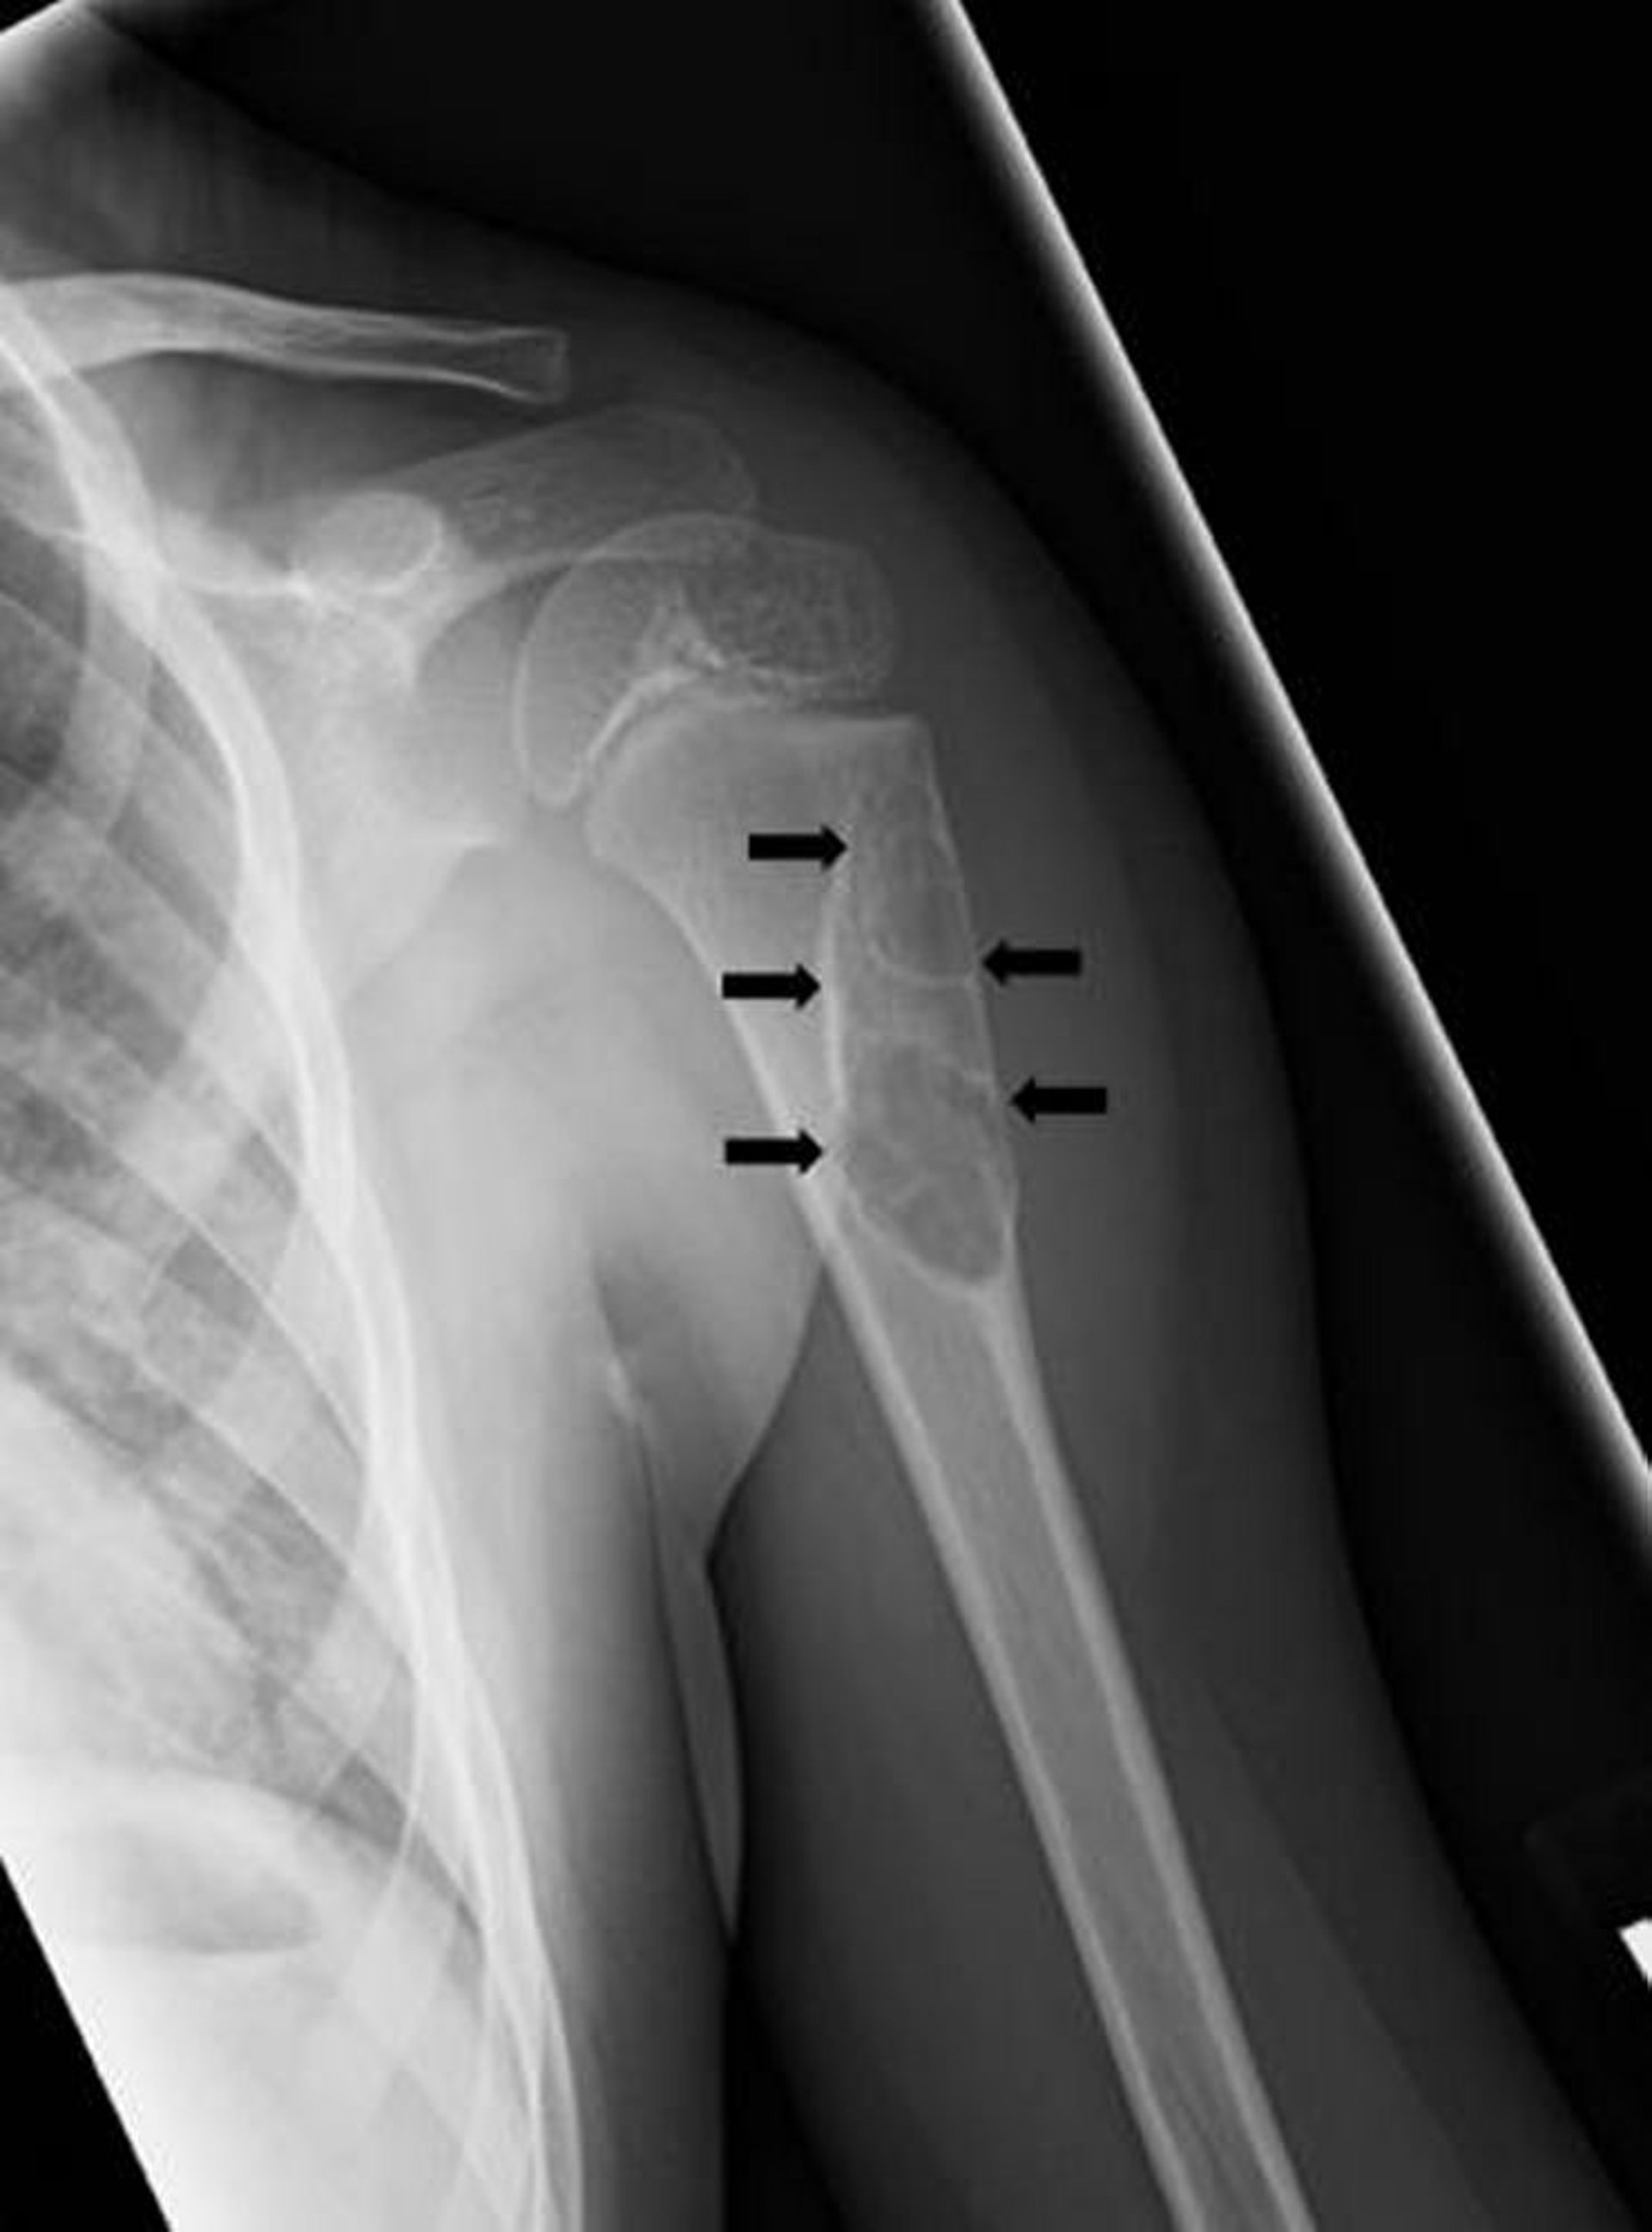

Einkammerige Knochenzyste

Diese Röntgenaufnahme zeigt eine zystische Läsion (Pfeile) des Humerus bei einem Kind, die mit einer einkammerigen Knochenzyste übereinstimmt.

Image courtesy of Michael J. Joyce, MD, and Hakan Ilaslan, MD.